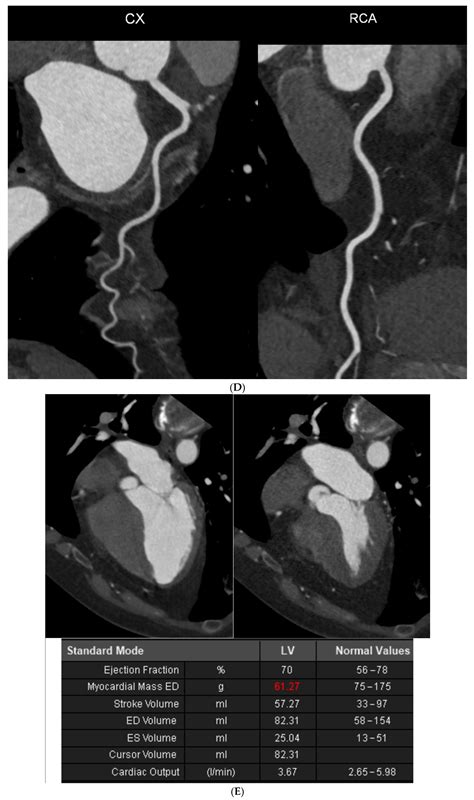

Discrepancies between Coronary Artery Calcium Score and Coronary Artery ...

3276Γ—5534